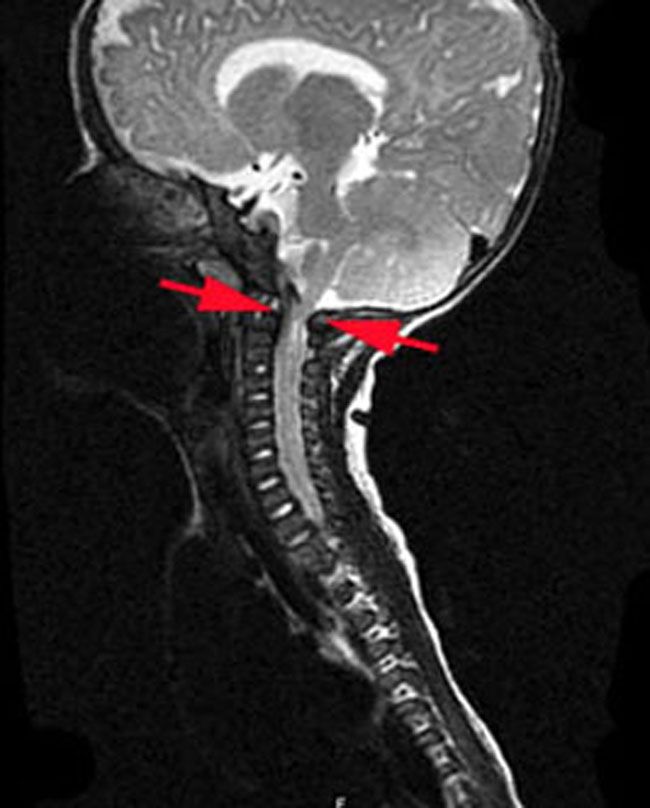

Compression of the upper end of the spinal cord. In babies with achondroplasia, the opening at the base of the skull through which the brainstem and spinal cord pass (foramen magnum) is often too narrow. This can result in compression of the upper end of the spinal cord, which can lead to muscle weakness and breathing problems. For a small number of babies with achondroplasia, this spinal cord compression can be life-threatening.

Your child's doctor may order an MRI scan of your baby’s spine to check the size of the foramen magnum. If it is too narrow, you may be referred to a neurosurgeon who can perform a surgical procedure called decompression to make more room for the spinal cord to pass through the opening in the skull.

X-ray of spinal cord compression

In this MRI scan of a 5-month-old girl with achondroplasia, the opening at the base of the skull is too narrow and is compressing her spinal cord.

Reproduced from Carter CW, Sharkey MS: Contemporary management of the pediatric patient with achondroplasia. Orthopaedic Knowledge Online Journal 2014; 12(1). Accessed July 2018.